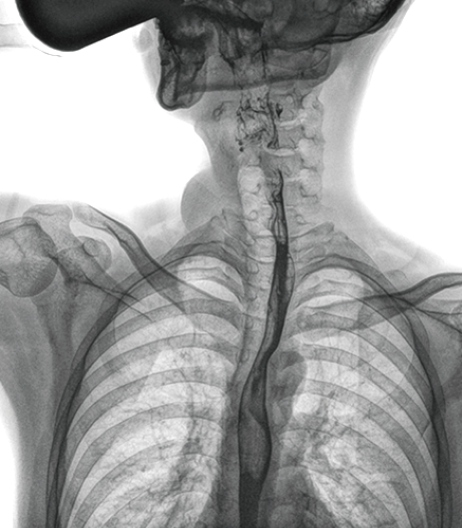

動態(tài)DR具有視頻保存、回放功能,可以完整的記錄整個透視動態(tài)圖像,便于重復(fù)觀察、分析,減少遺漏。該功能在食道造影中優(yōu)勢明顯:患者口服造影劑后流速很快,傳統(tǒng) DR 的盲拍或是數(shù)字胃腸造影很難抓拍到,需要患者反復(fù)喝造影劑,而動態(tài) DR 視頻實時保存回放,既減少漏診誤診又減輕患者痛苦,也更加節(jié)省醫(yī)生時間。

上消化道造影高清圖像